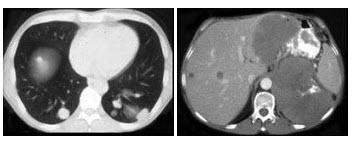

33、多项选择题

男,53岁,体重明显下降而行CT检查,如图所示,下列说法正确的是()

A.右肾区可见不规则的软组织块,增强为不均匀强化

B.肾平面以上的下腔静脉内均有软组织密度影

C.右心房内可见充盈缺损

D.此为右侧肾癌

E.癌栓侵入下腔静脉并扩散至右心房